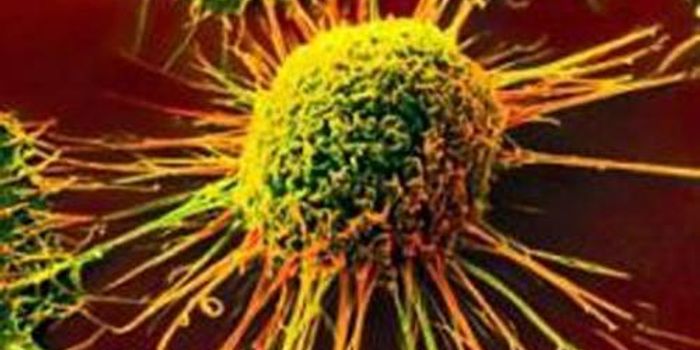

FEB 12, 2019CancerCancer is on everybody's mind these days. Many pharmaceutical companies are devoted solely to finding new cancer tre ...

APR 06, 2015CancerNorthwestern Medicine scientists have identified a small RNA molecule called miR-182 that can suppress cancer-causing ge ...

MAR 31, 2015CancerFasting in combination with chemotherapy has already been shown to kill cancer cells, but a pair of new studies in mice ...

JUN 05, 2018CancerSo often the phrases "Precision Medicine" and "Personalized Medicine" are used interchangeably. Are they really synonym ...

APR 14, 2015CancerAn experimental drug that attacks brain tumor tissue by crippling the cells' energy source called the mitochondria has p ...

FEB 26, 2015CancerA study published in Science Translational Medicine showed that immune cells engineered to seek out and attack a type of ...